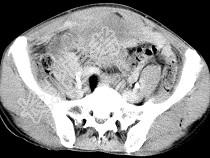

- 单项选择题男,56岁, 无规律上腹痛,左锁骨上淋巴结肿大, 消瘦、乏力,影像检查如图, 最可能的诊断是 ( )

C、胃癌并盆腔种植